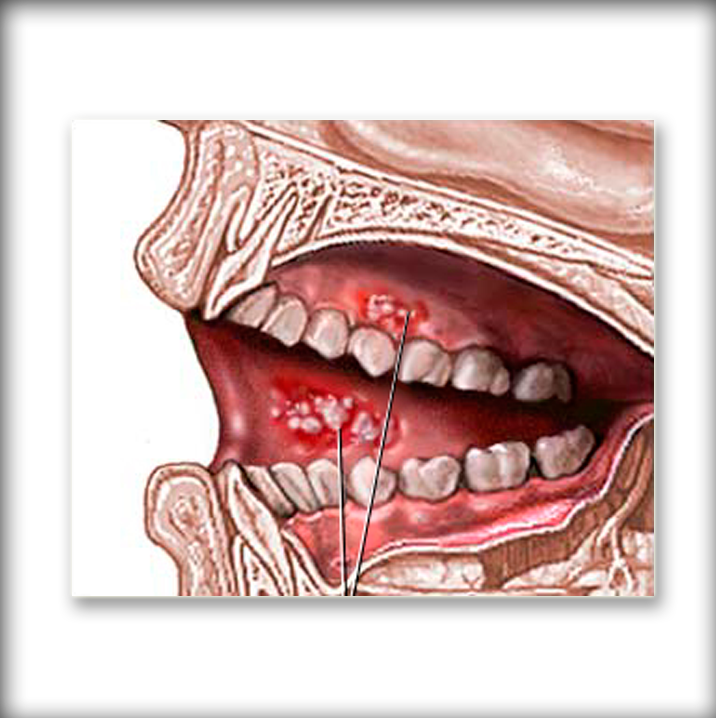

- Ver expedienteDiagnostico de Cancer Oral